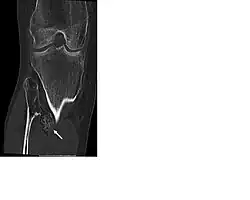

Karakteristiek zijn de (vele) in principe goedaardige bottumoren (exostosen; osteochondromen) die voorzien zijn van kraakbeenkap en waarbij de mergholte verbinding heeft met die van het betreffende bot. Ze zijn vrijwel altijd gelokaliseerd rondom een gewricht en worden bij HME in tegenstelling tot bij het solitaire osteochondroom niet beschreven in de schedel of het aangezicht. Het osteochondroom kan gesteeld of breedbasisch zijn en heeft altijd een groeirichting van het gewricht af. De exostosen ontstaan vaak al op zeer jonge leeftijd (peuter- of kleuterleeftijd) en groeien vooral tijdens de groeileeftijd erg hard. Ze veroorzaken regelmatig vergroeiingen, groeistoornissen, bewegingsproblemen en pijn. Met name bij lokalisaties rondom de knie wordt een pijnlijke bursa onder de aanhechting van de hamstrings pes anserinus op het scheenbeen beschreven. Pijnklachten als gevolg van tractie op de zenuwen of pezen wordt ook frequent gezien.[2] Lokalisaties van osteochondromen in de pols kunnen ernstige deformiteiten (verkorting van de ulna en bowing van de radius) veroorzaken (39-60%). In 10-50 % van de patiënten wordt een beenlengteverschil beschreven en in 8-33% varus-valgus angulatie van de knie (O- of X-benen).[2] Grote gesteelde osteochondromen, met name in de onderste extremiteit, lopen de kans af te breken bij lichamelijke activiteiten of ongevallen. Dit wordt in ongeveer 5% van de gevallen beschreven. Ten slotte wordt soms een afwijkende wondgenezing bij HME-patiënten beschreven.

HME wordt vaak vastgesteld aan de hand van röntgenfoto's. In het algemeen wordt aangenomen dat men kan spreken van een HME-MO als er meer dan 2 exostosen/osteochondromen bestaan. Aanvullend onderzoek kan nodig zijn in de vorm van een CT-scan, een nucleaire bot-scan of MRI-scan om zo nog onbekende lokalisaties (bv achter de scapula of in het bekken/wervelkolom) van osteochondromen te diagnosticeren. Een MRI scan van de exostose zelf kan worden gebruikt om de dikte van de kraakbeenkap bij volwassen patiënten te meten. Een kraakbeenkap dikker van 1 cm kan een aanwijzing zijn voor maligne degeneratie. Verder worden op een MRI-scan de aanwezigheid van; een weke delenuitbereiding, in het bijzonder als er verkalkingen in de weke delen bestaan, een onregelmatig oppervlak of een 'septal and ring enhancement pattern' van de kraakbeenkap en cortexdestrucie gezien als kwaadaardige radiologische kenmerken. Na de puberteit (na het sluiten van de groeischijven)ontstaan er geen nieuwe exostosen meer en behoren bestaande exostosen niet te groeien. Is er na de puberteit toch sprake van pijn of groei is het verstandig extra onderzoek in de vorm van een MRI-scan te verrichten. Veelal werd een botscan gebruikt om een kwaadarige ontaarding van een osteochondroom te beoordelen. Deze kan alleen niet differentiëren tussen een actieve kraakbeenkap met enchondrale kraakbeen afzetting en kwaadaardige ontaarding. Met het intreden van het gebruik van de MRI-scan is de beoordeling van de kraakbeenkap dan ook sterk verbeterd.